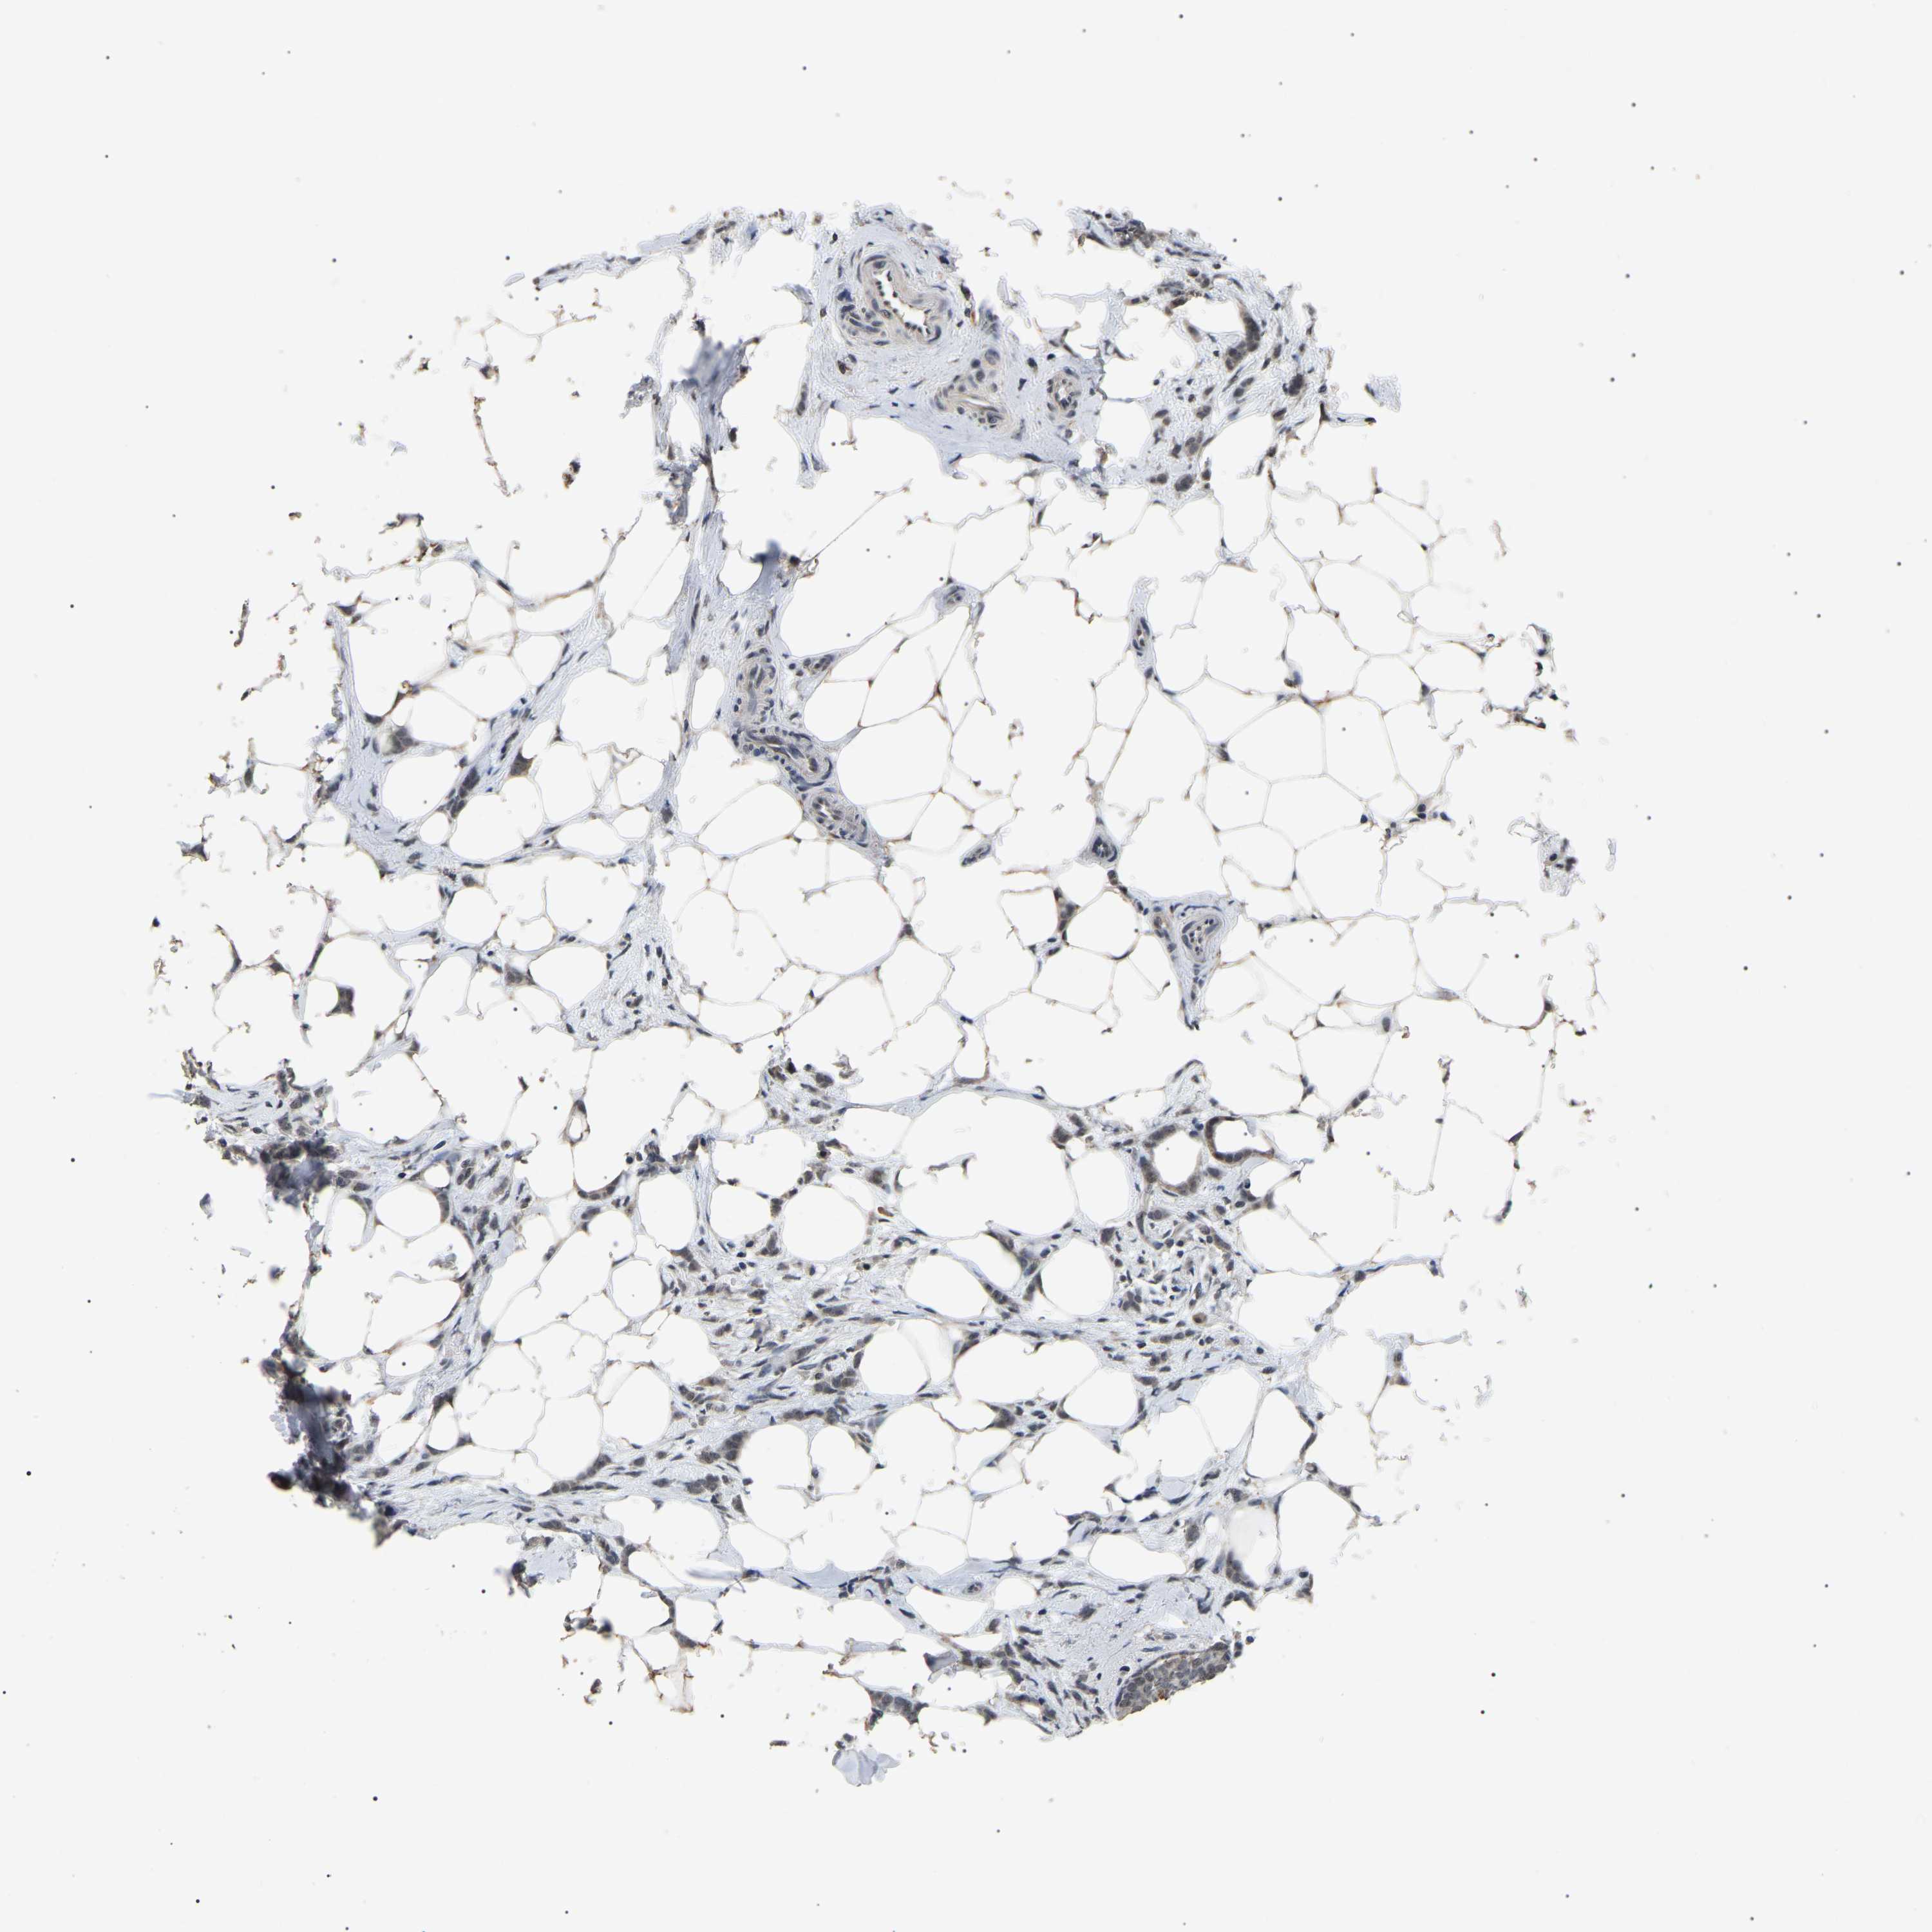

Breast cancer

Human cancer